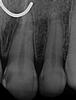

Our Vienna, VA dentists plan treatment using a digital x-ray image of the tooth. We may also recommend a 3-D digital scan of the tooth using CT cone beam technology. This valuable technology provides more information than a two-dimensional x-ray and allows for more precise treatment planning.

When we begin your root canal treatment, we first open a small hole in your tooth to access the root canal. Dr. Sanati and Dr. Sharahm use leading-edge rotary endodontic technology to gently and quickly remove the infected material. Instead of the manual steel files dentists used in the past, rotary endodontics employs an electrically-powered instrument that allows us to perform more efficient and comfortable root canals with a higher success rate for our patients.

When our Tysons dentists have cleared away every trace of the infection, they fill the hollowed-out space with an inert material called gutta-percha and then seal the tooth. Since there is no more blood supplying the tooth, it will become brittle, so we may recommend a dental crown to protect it. If you don't need a dental crown, we will still need to place a filling on the tooth to restore and strengthen it.